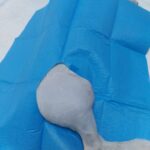

Mjekim i gabuar

Qeni ne foto erdhi ne klinike me diarre te shoqeruar me hemoragji. Ishte kontrolluar ne nje spital ku nuk u konstatua qe ai ishte i helmuar dhe si rjedhoje ishte trajtuar me mjekim te gabuar. Pas mjekimit intensiv 3 ditor ai shpetoi dhe e kaloi rrezikun. Sikurse shikohet ne foto u ngrit ne kember dhe filloi te ushqehet vete normalisht.